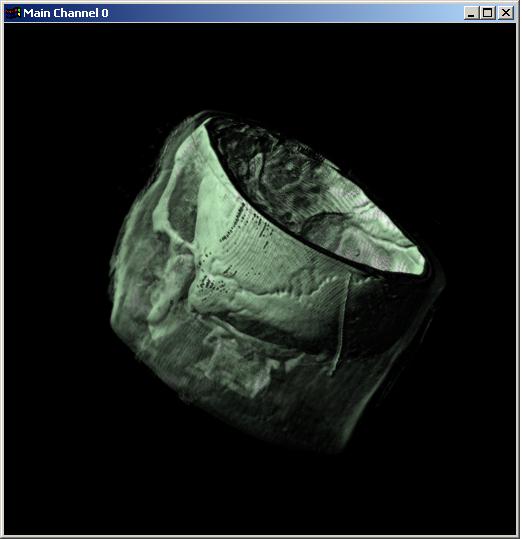

Visible human male CT data

Bone only

Data Resolution : 256x256x128

The following 12

images was generated by PC which has NVIDIA's GeForce3 GPU graphics card. The

hardware accelerated rendering techniques are used to make the following images.

To use the GeForce3 hardware, we have to use the OpenGL extensions like

GL_NV_texture_shader2, GL_NV_register_combiners, GL_EXT_texture3D,

GL_EXT_paletted_texture, GL_ARB_multitexture and so on. Since the GeForce3 card

allows the 3D texture shading, the image quality is better than the pixel of

frame buffer based shading in showing two materials at the same time.